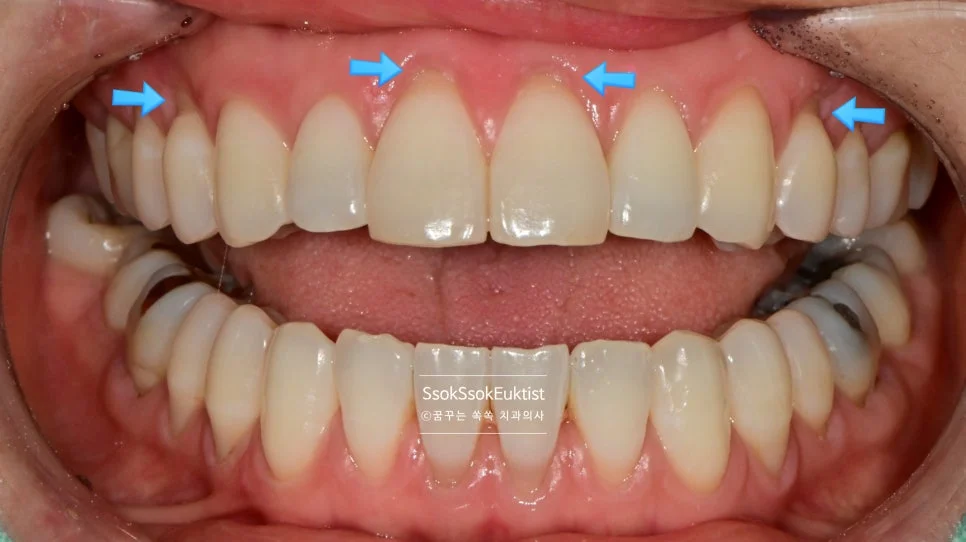

화살표로 표기된 치료 계획 — 앞쪽은 레진, 어금니는 GI

화살표로 표기된 것과 같이 눈에 보이는 앞 쪽 치아는 레진으로, 큰 어금니는 GI로 계획을 세웠는데요.